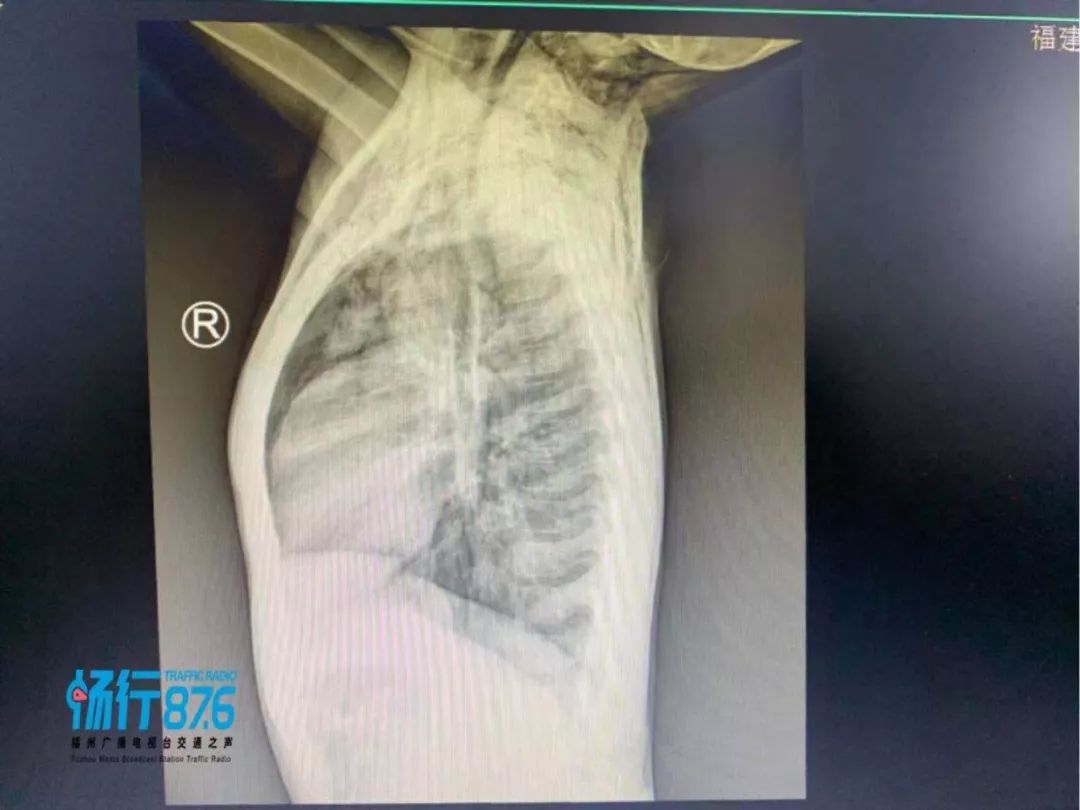

医生所说的“纵隔气肿”是一种罕见的疾病,紧接着孩子被送进了监护室,通过吸氧、止痛、镇静、雾化、止咳、补液抗炎等对症治疗,经过和内科医生会诊,调整了治疗方案,期间复查复查颈胸CT及咽拭子病毒监测,提示颈部、纵隔、胸壁、上腹部皮下软组织多方积气、右肺炎症、双肺间质积气。

找到了原因,经过6天的治疗后,目前孩子颈部无疼痛,体温正常,咳嗽及气喘好转,一般情况良好,近日复查CT提示颈部及纵隔内气体大部分吸收,过几天康复后即可出院。